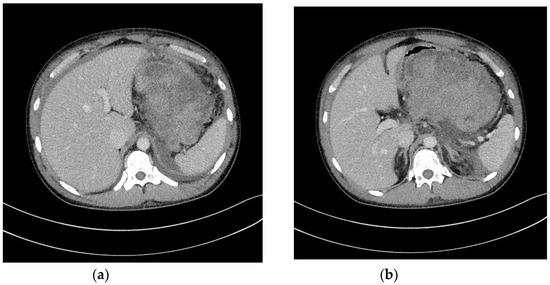

- Jagielski, M.; Smoczyński, M.; Jabłońska, A.; Marek, I.; Dubowik, M.; Adrych, K. The role of endoscopic ultrasonography in endoscopic debridement of walled-off pancreatic necrosis—A single center experience. Pancreatology 2015, 15, 503–507. [Google Scholar] [CrossRef]

- Smoczyński, M.; Marek, I.; Dubowik, M.; Rompa, G.; Kobiela, J.; Studniarek, M.; Pieńkowska, J.; Adrych, K. Endoscopic drainage/debridement of walled-off pancreatic necrosis—Single center experience of 112 cases. Pancreatology 2014, 14, 137–142. [Google Scholar] [CrossRef] [PubMed]

- Jagielski, M.; Smoczyński, M.; Studniarek, M.; Adrych, K. Endoscopic drainage combined with percutaneous drainage in treatment of walled-off pancreatic necrosis- a single center experience. Prz. Gastroenterol. 2018, 13, 137–142. [Google Scholar] [CrossRef] [PubMed]

- Jagielski, M.; Smoczyński, M.; Jabłońska, A.; Adrych, K. The development of endoscopic techniques for treatment of walled-off pancreatic necrosis (WOPN)—A single center experience. Gastroenterol. Res. Pr. 2018, 24, 36–41. [Google Scholar] [CrossRef] [PubMed]